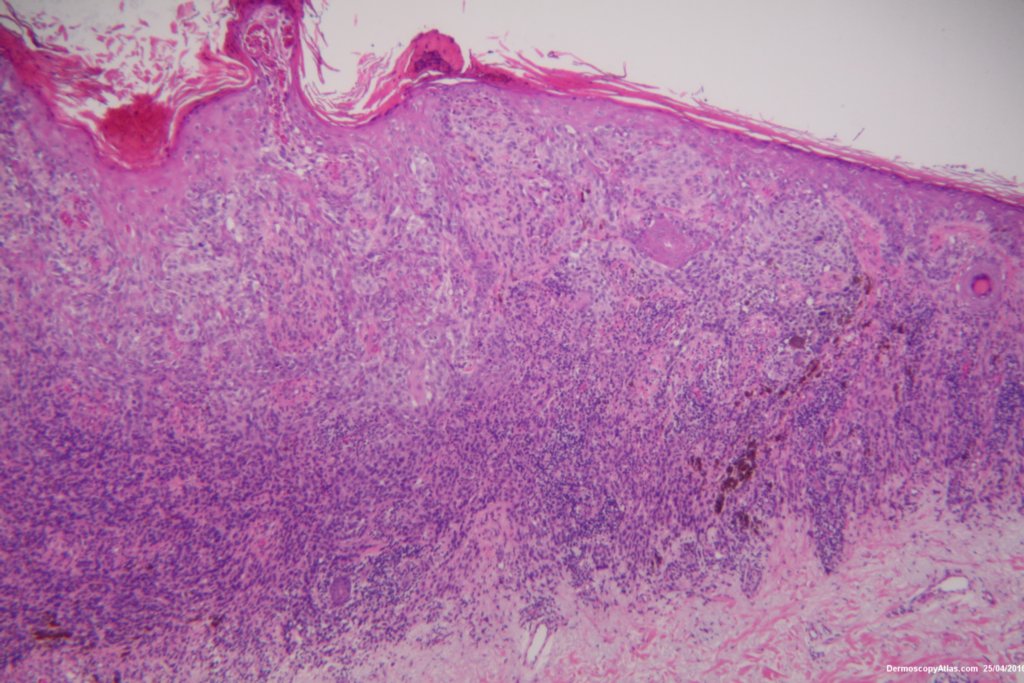

Image Number #3392 (Melanoma invasive)

Diagnosis: Melanoma invasive

Description: Lesion on the thigh

This 57 years old male presented with a lesion on his thigh that he said had only been present for 6 weeks. It looked and felt keratotic and had a bluish discolouration associated with it. It was thought to be an irritated Seborrhoeic keratosis perhaps with some bleeding into it to account for the blue colour.

The shave biopsy was reported as a level 4 Invasive melanoma 1.7 mm thick with 3 mitoses per high powered field. There were no groin glands enlarged clinically.